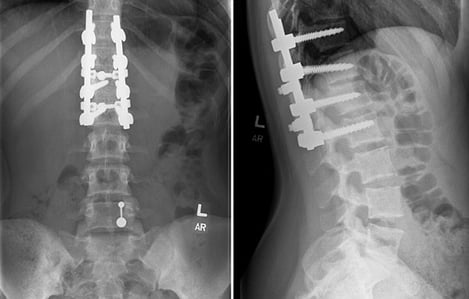

With Dr. Lew primarily concentrating on the spinal cord and Dr. Tassone on the spinal column, the two together performed a nearly five-hour spinal fusion surgery. Through a 12-inch incision along her back, Dr. Tassone realigned Karina’s spine and attached two cobalt chromium rods and eight screws to hold it in place. Meanwhile, Dr. Lew focused on any compression or damage to the spinal cord and other nerve elements.

She was recently back for her six-month follow-up X-ray and she is progressing nicely. In the coming years, her vertebrae should continue to grow together and strengthen. She’ll continue to receive therapy to work on her balance, coordination and strength, and in six months she’ll be back for another follow-up X-ray. If everything continues to look good, she’ll move to annual exams.